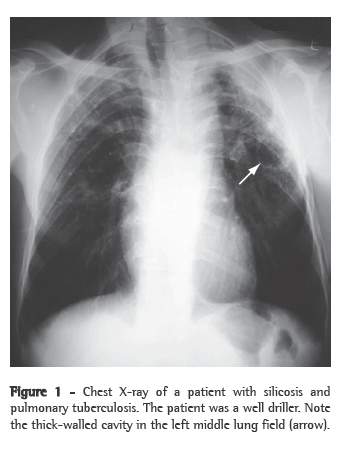

As an initial additional evaluation, it is recommended that sputum smear microscopy and sputum culture (induced sputum culture, if necessary, since it has good sensitivity) be performed, as well as chest X-ray,(23,26) as shown in Figure 1. In cases in which there are still doubts about the presence of active tuberculosis, bronchoscopy with BAL can be used, in conjunction with transbronchial biopsy when possible; biopsies significantly increase the diagnostic yield of the test, even in patients whose sputum and BAL are negative for mycobacteria.(27)